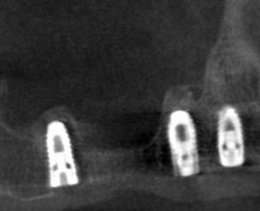

サイナスリフト症例(治療前後のCTもしくはパノラマ写真)

↓

↓